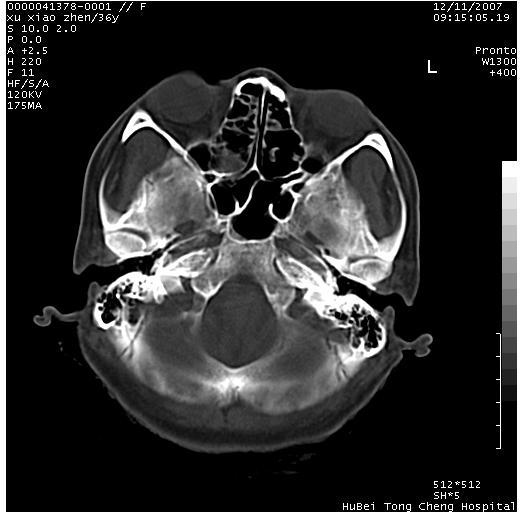

以下是引用wzr在2007-12-12 18:58:00的发言:[br]以脑白质受累,脑肿胀明显,脑室变窄,多考虑炎性改变,建议进一步ce或mri明确.

以下是引用wqs571018在2007-12-12 19:48:00的发言:[br]脑白质受累,脑肿胀明显,脑室变窄,多考虑炎性改变,脑膜炎可能性大;建议mri明确.。